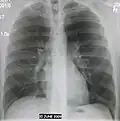

Normal lateral CXR -